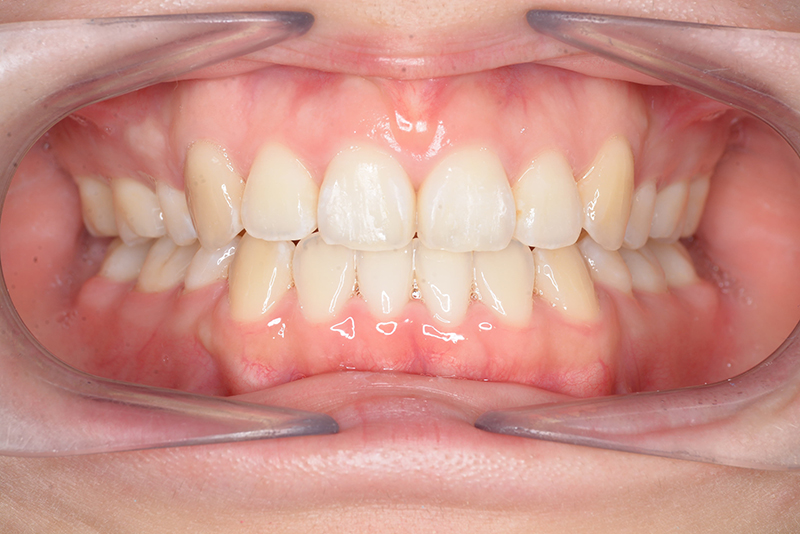

| 主訴 | 前歯のでこぼこ | 診断名 | アングルⅠ級叢生症例 | ||||

| 初診時年齢 | 24歳11ヵ月 | 性別 | 女 | 動的治療期間 | 20ヵ月 | ||

| 口腔内所見 | over jet 4.5mm、over bite 4.0mm、大臼歯関係 I級で上下顎前歯部に叢生が認められた。 |

| 批評・予后 | 叢生が大きかった影響もあり、治療期間は20ヶ月と比較的短い期間が終了できた。治療後においては口元の改善、咬合の緊密化は達成できたように思う。 |